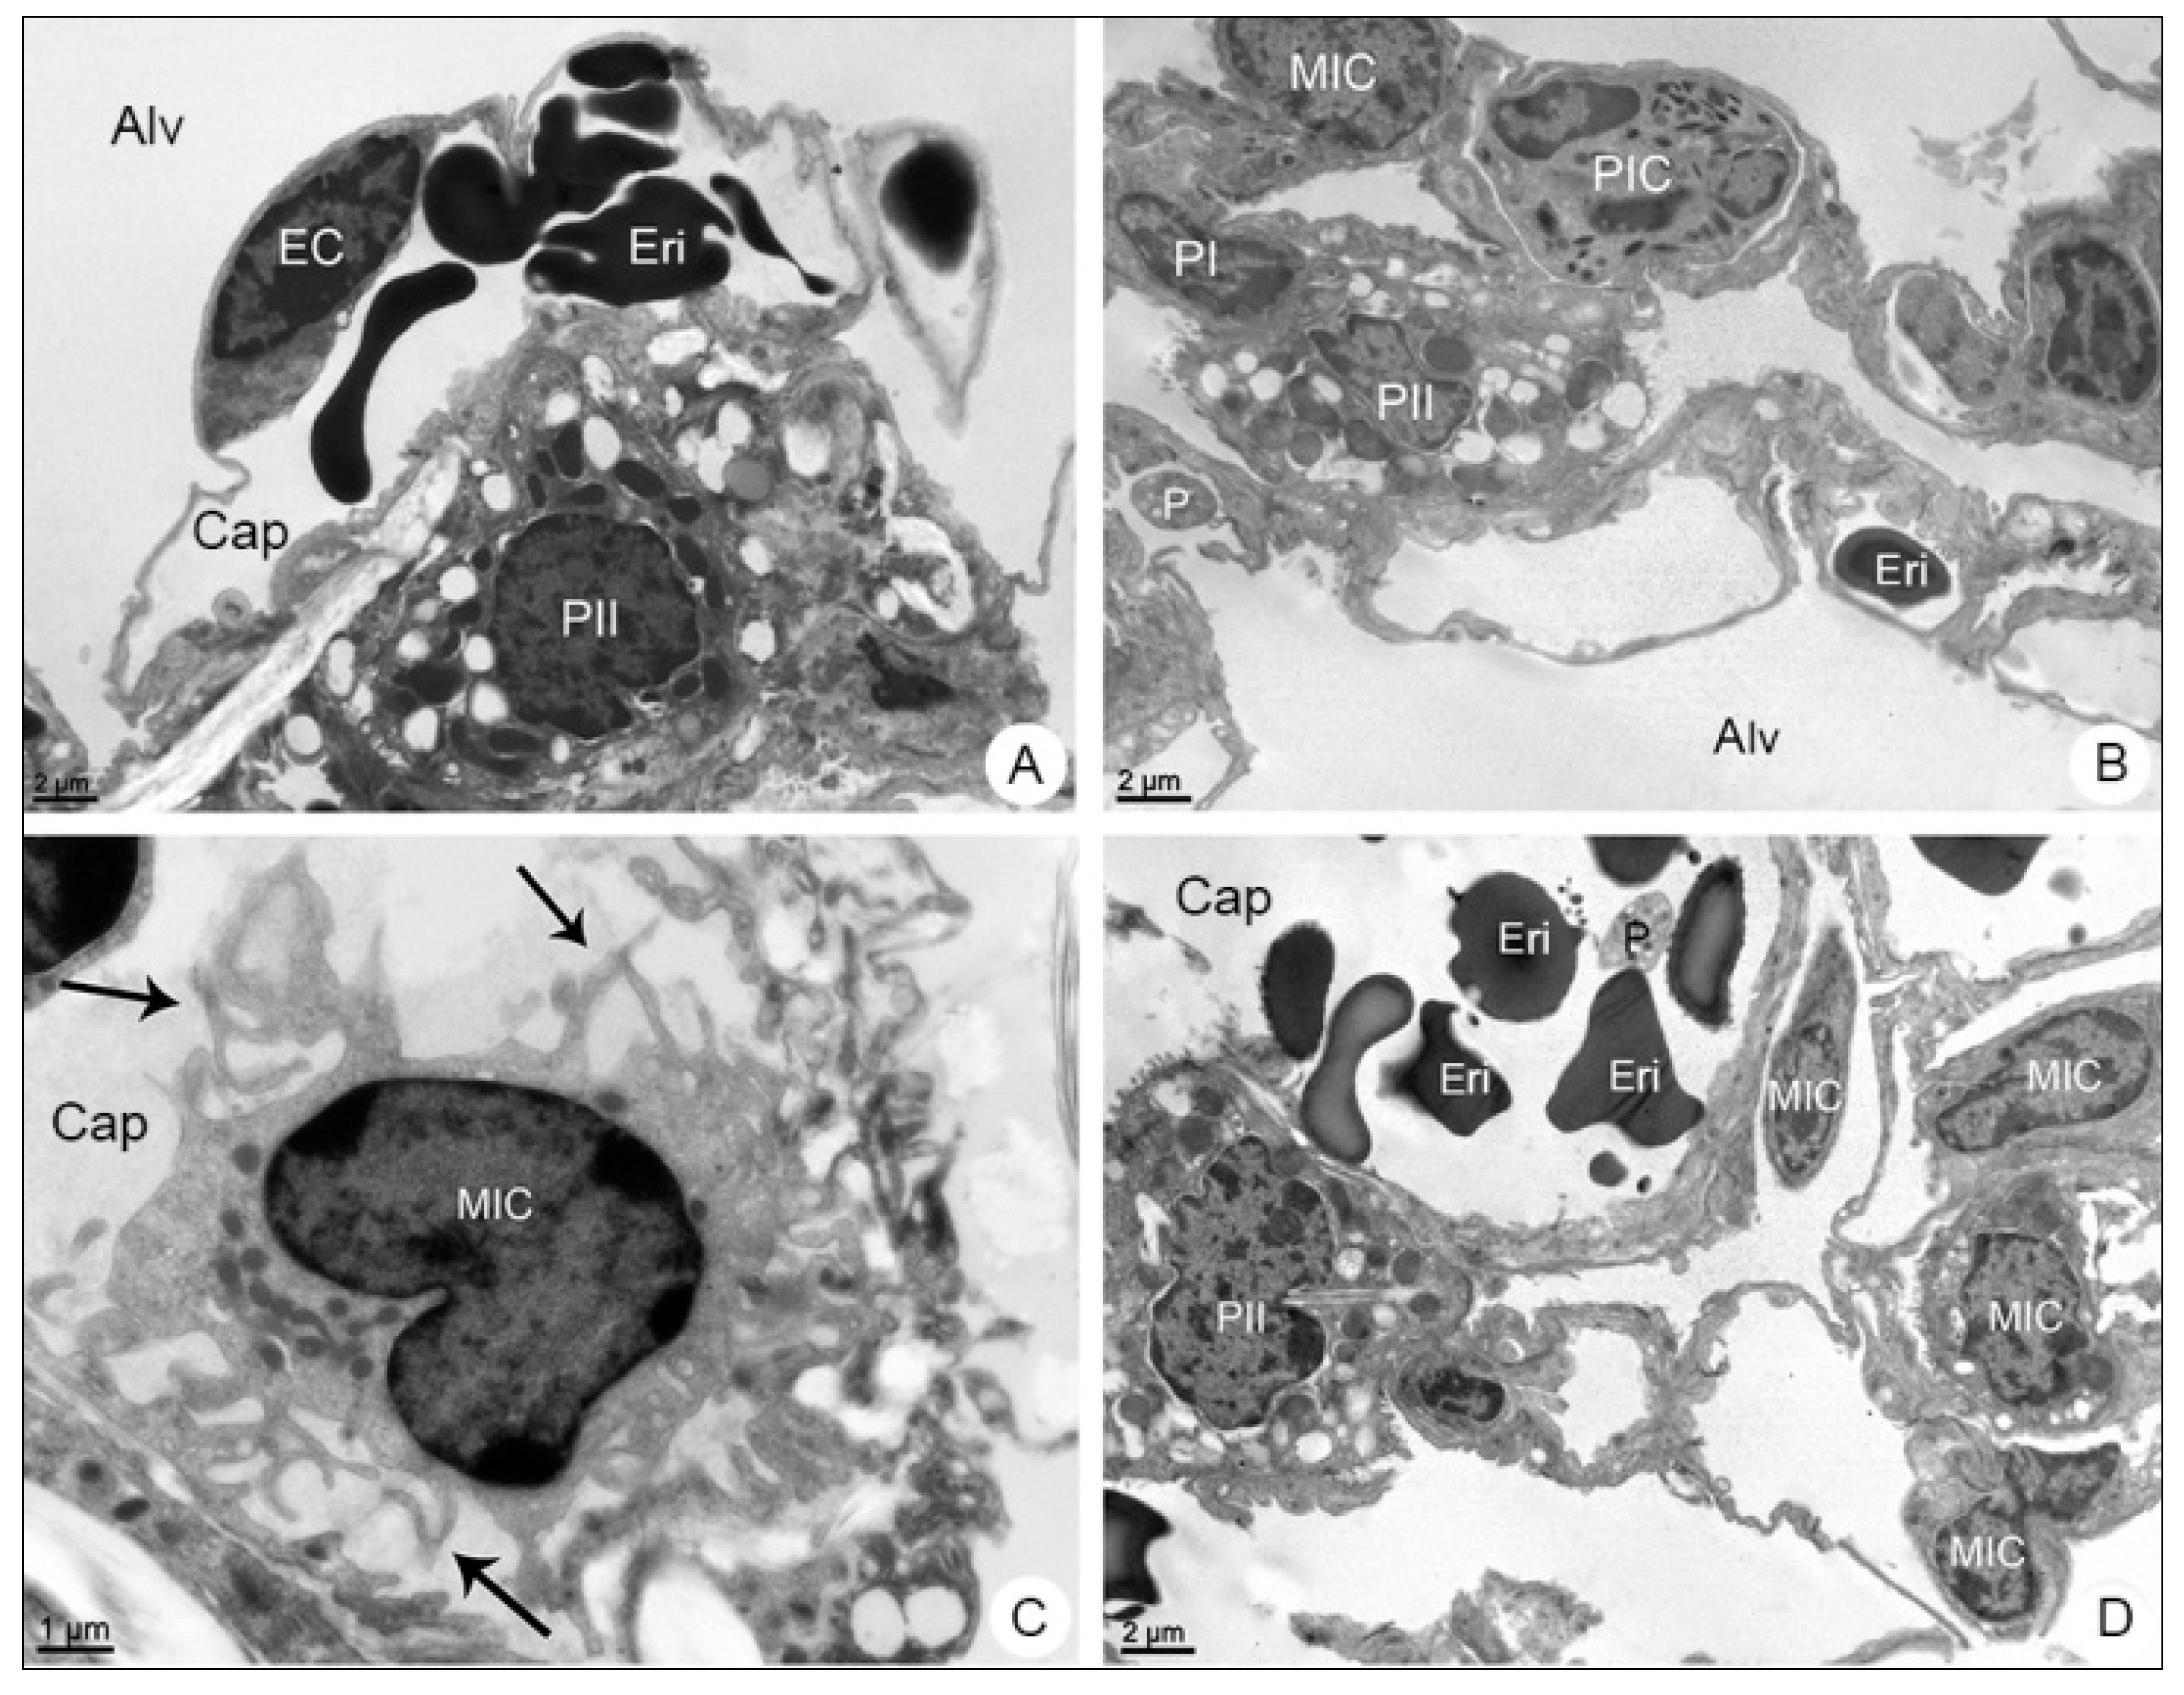

3.2.2. Lung Samples